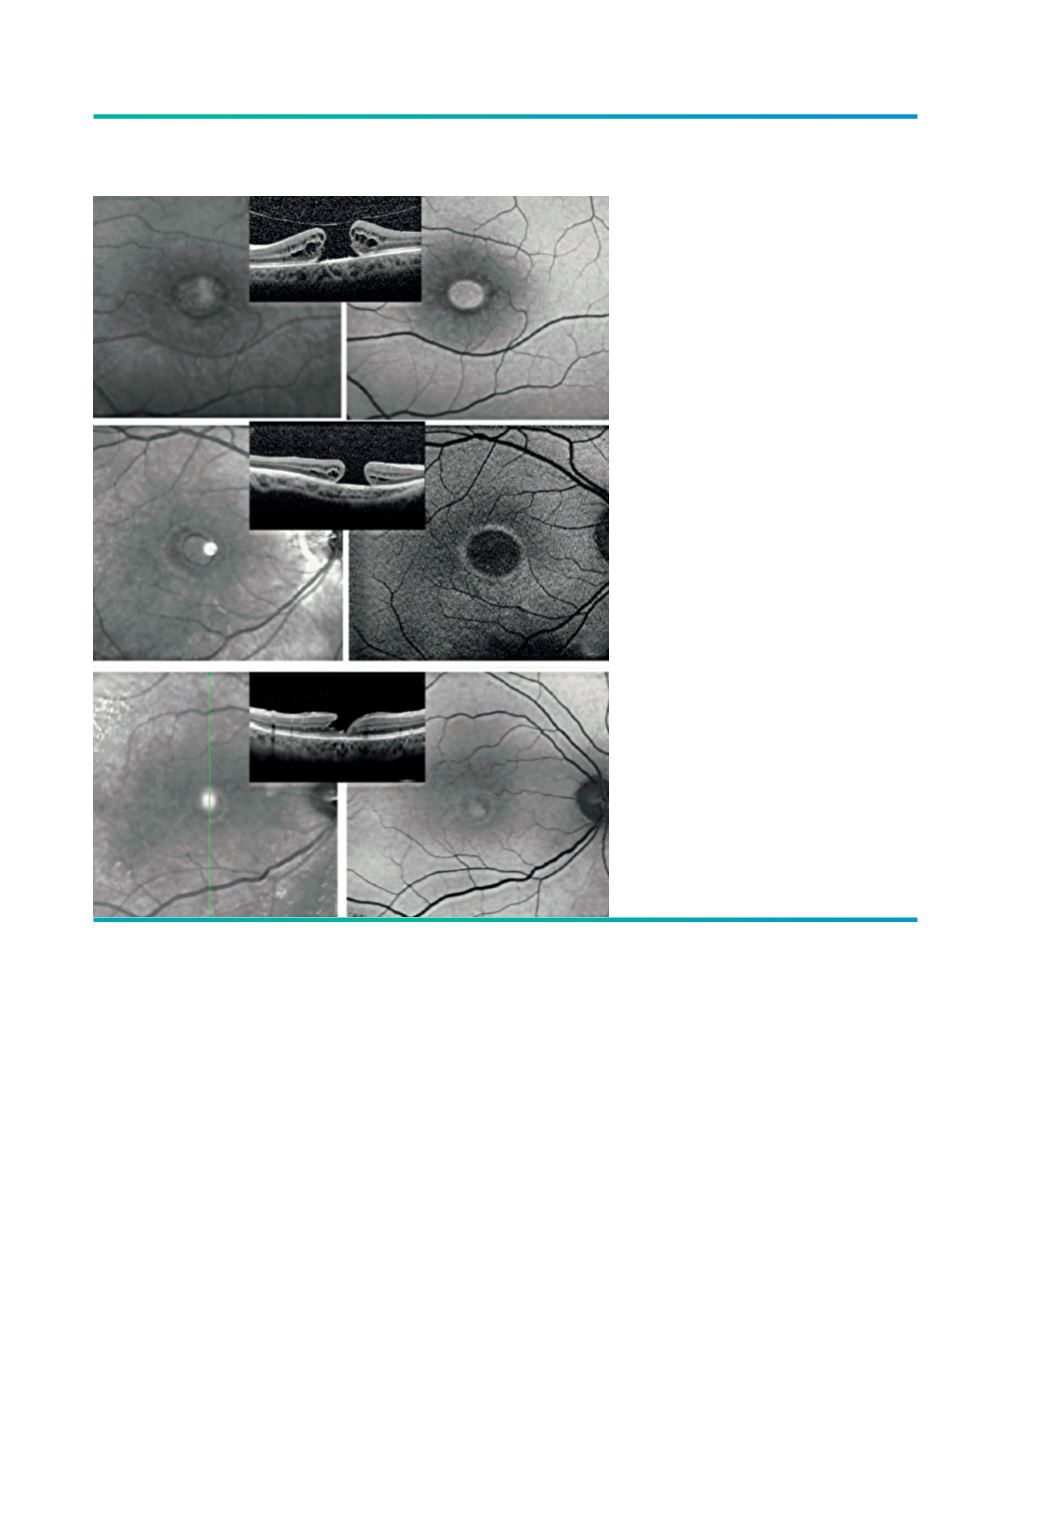

Figura 3.

A e C) BM grande, com aderência

vítrea focal. B) A autofluorescência

evidencia uma área central de

hiperAF correspondendo ao

buraco, rodeada de anel hipoAF

pela presença de fluído sub-

retiniano e de outro anel mais

excêntrico de relativa hipoAF, onde

se identifica um padrão estrelado,

com estrias radiárias hipoAF (seta

vermelha), resultado de cistos intra-

retinianos na plexiforme externa.

D e F) – Buraco macular grande,

com longo tempo de evolução,

E) Padrão de hipoAF marcada,

resultando de atrofia secundária

do EPR no leito do buraco macular

e no anel circundante. O halo

hiperautofluorescente corresponde à

transição para um EPR normal.

G e I) Buraco lamelar com

proliferação epirretiniana (LHEP), H)

Evidencia-se uma hiperAF central

muito mais ténue correspondendo ao

buraco central.